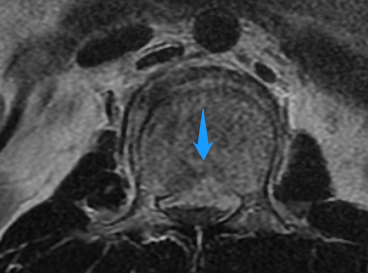

手术后当天,姚某右下肢已可轻微活动,经过1月余的专科康复后,姚某已可拄拐下地站立。他激动地说,“我以为自己将永远躺在床上了,想不到医生还能让我站起来,非常感谢医护人员高超技术和精心照顾。” 腰椎术前X线侧位片 术前磁共振 术前磁共振显示神经明显受压 姚某术后恢复情况 薛厚军副主任医师指出,脊柱骨折是临床常见脊柱损伤,发病群体是青壮年,指的是因外力对脊柱骨质造成连续性的破坏、高处坠落、车祸等高能量损伤是导致脊柱骨折的主要原因。对于严重的脊柱爆裂性骨折,可以造成脊髓或神经的损伤,导致肢体运动感觉障碍或者瘫痪,严重影响病人的生存及生活质量。所以,只要条件允许,应尽早手术治疗。 随着科技的进步以及人们自我保护意识的提高,近年来脊柱骨折的病人已有所减少,但对于其引起的严重后果我们仍不能忽视。建议广大民众出现脊柱骨折后要就近在有实力的医院诊治,搬动要严格轴线平抬,避免二次伤害,以免延误病情。